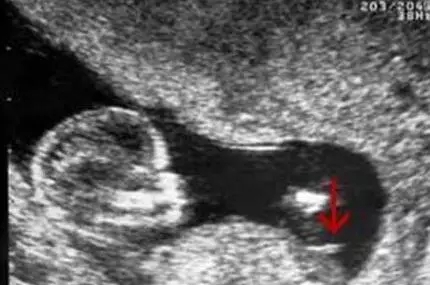

2017生男生女计算器

这个是网上一位妈妈晒得女女的B超图片,可以看到图片中在中间很明显木有小鸡鸡,是一位女宝宝的部位。